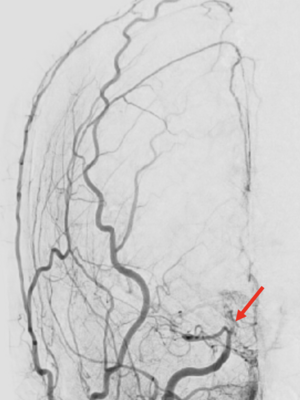

The FDA approval of flow diversion technology in 2011 revolutionized the treatment of intracranial aneurysms. The use of this technology has rapidly evolved, extending beyond paraclinoid aneurysms to include the treatment of distal and complex aneurysms, even those located in the posterior circulation. Our research focuses on establishing the safety and efficacy of flow diversion for both FDA-approved and off-label use, factors determining treatment failure, complications, adjustments to dual antiplatelet therapies, and ideal imaging follow-up intervals. We have also explored biological mechanisms predicting response after treatment and collaborated with multiple institutions nationwide in various registries and clinical protocols.